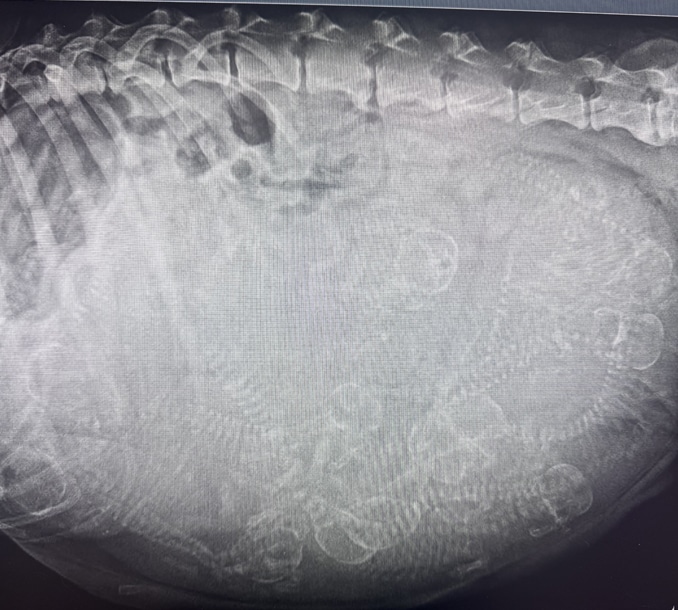

Guess how many puppies?

Digital X-Rays (Radiography)

Whether your pet is limping or having trouble breathing, radiographs (X-rays) give us a clear view of what’s happening internally. These high-resolution digital images help us detect:

With digital imaging, we can adjust image quality instantly, zoom in on problem areas, and share results with specialists if needed—all without waiting for film to develop.